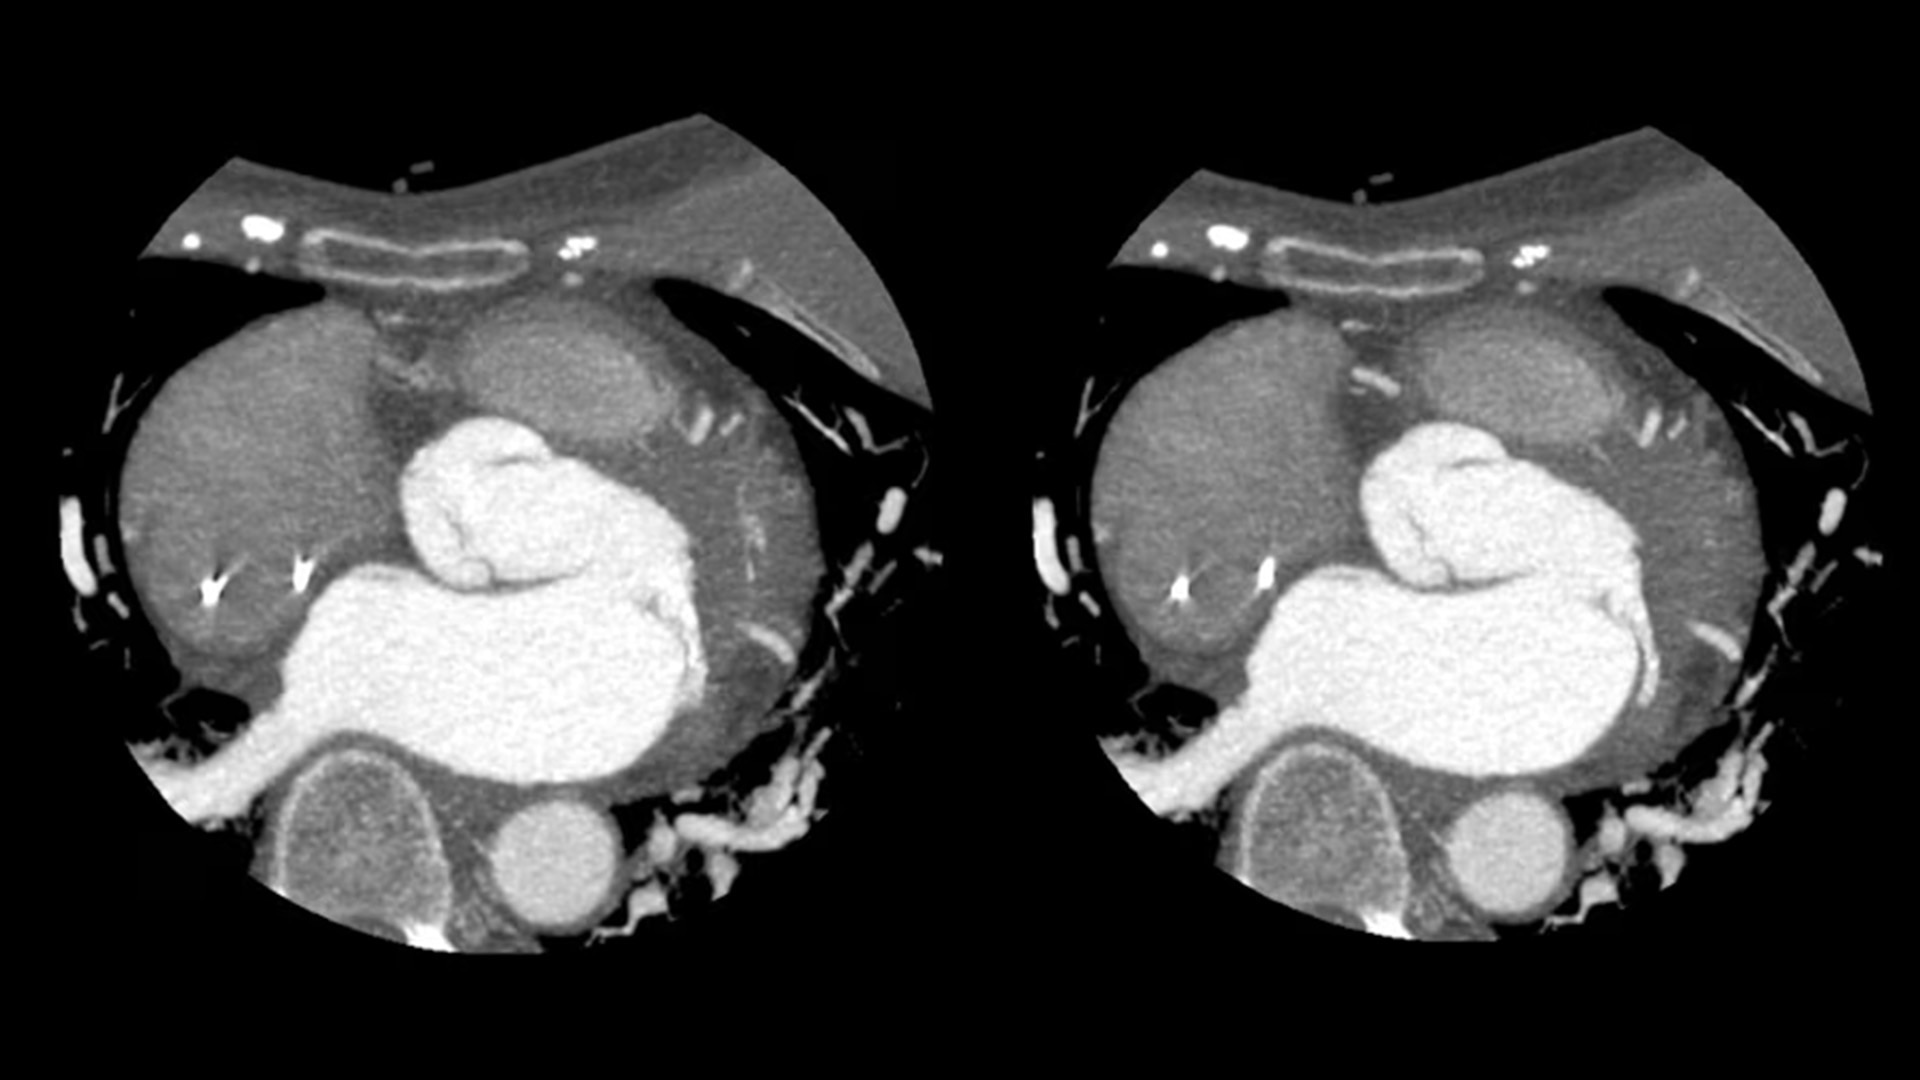

SnapShot Freeze 2

Intelligent and automated whole-heart motion correction for enhanced Cardiac CT imaging.

Motion correction

6x reduction in motion artifacts1

Temporal resolution

19.5 msec effective temporal resolution at 0.23s/rotation gantry speed2